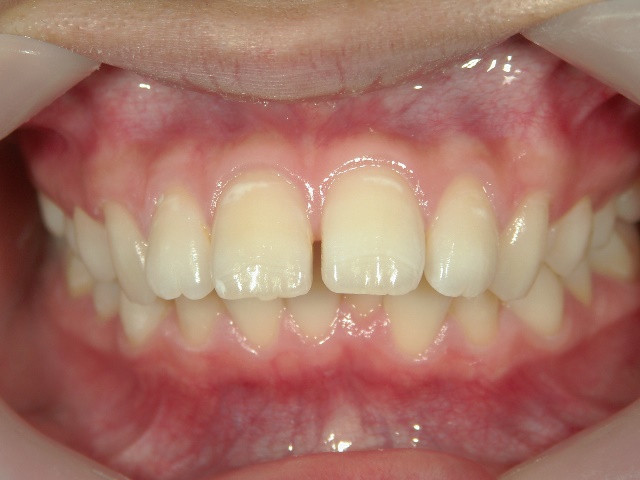

矯正歯科(全顎ワイヤー矯正)治療後

全顎ワイヤー矯正 症例(5)

20歳女性 浜松市東区

在住

治療期間2年4

ヶ月

矯正歯科 治療後